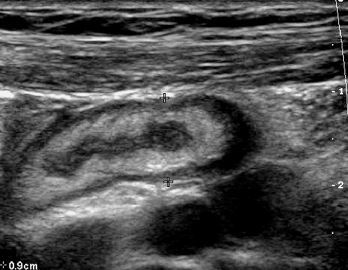

Transverse and longitudinal views of

the mediastinum of the testis